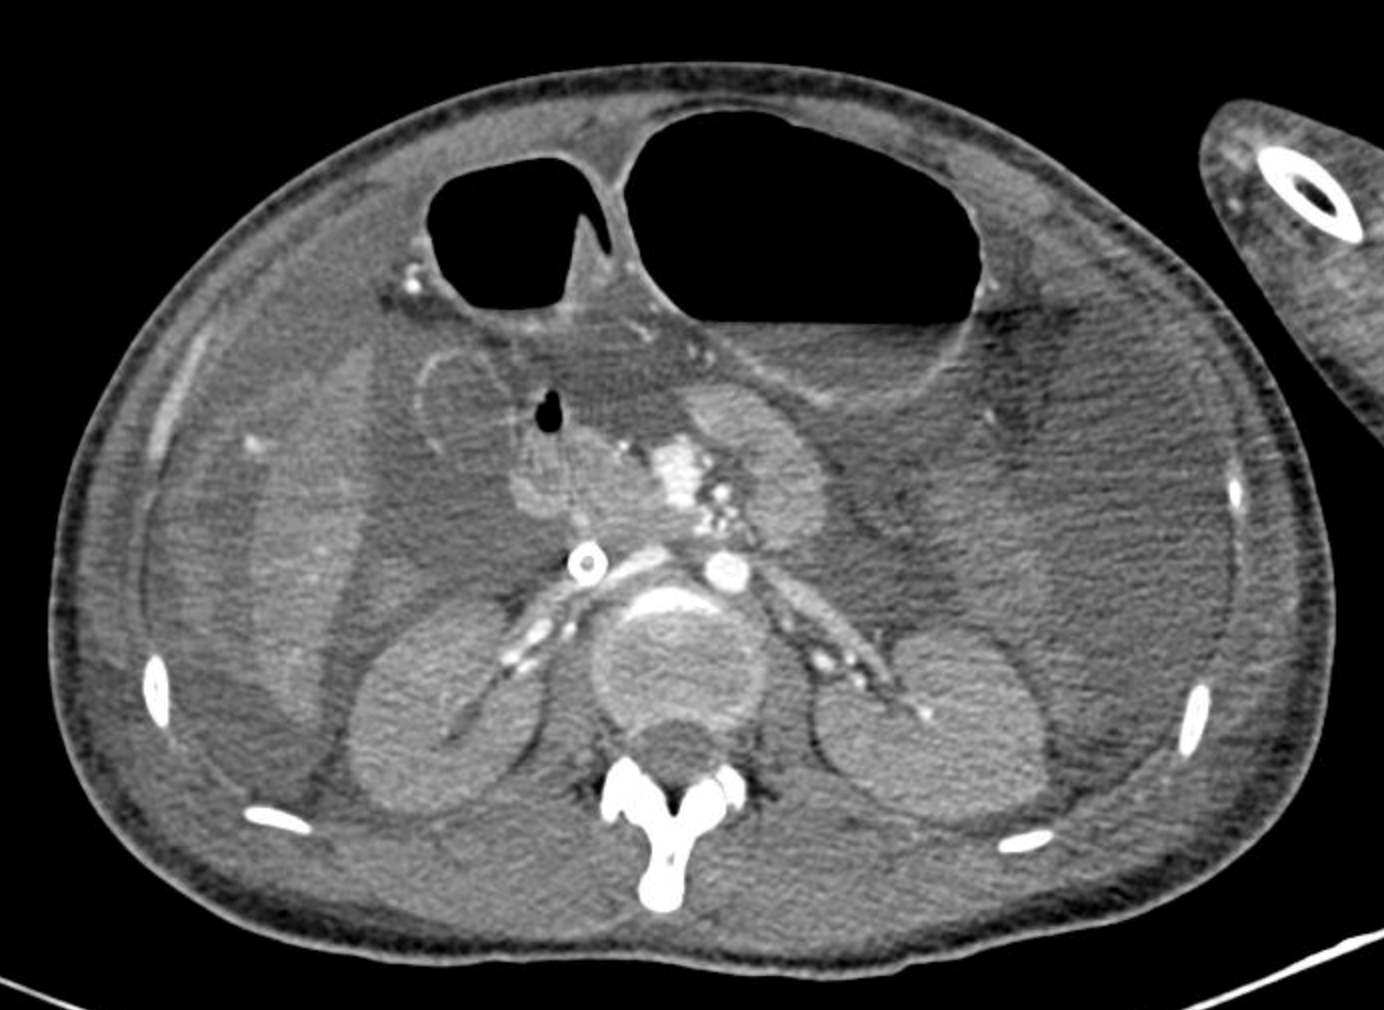

Dịch ổ bụng lượng nhiều, nghi ngờ chảy máu ổ bụng trên phim chụp cắt lớp vi tính.

Bên cạnh việc truyền máu tích cực, việc tìm nguyên nhân chảy máu là một vấn đề cấp bách được đặt ra, nếu không bao nhiêu lượng máu hiếm quý như vàng lại tiếp tục chảy ra. Hình ảnh trên siêu âm cũng như chụp cắt lớp cho thấy dịch ổ bụng lượng nhiều, nghi ngờ có máu trong ổ bụng. Người bệnh sau đó được nhanh chóng chuyển lên phòng mổ kèm theo hệ thống ECMO để can thiệp nội soi ổ bụng cấp cứu dưới sự thực hiện của BS. CKII Phan Lương Huy khoa Ngoại tổng quát. Nhờ sự can thiệp kịp thời và chính xác, ổ chảy máu được xác định nằm ở phân thùy VI của gan nhanh chóng được can thiệp đốt cầm máu, ca phẫu thuật bước đầu đã thành công.